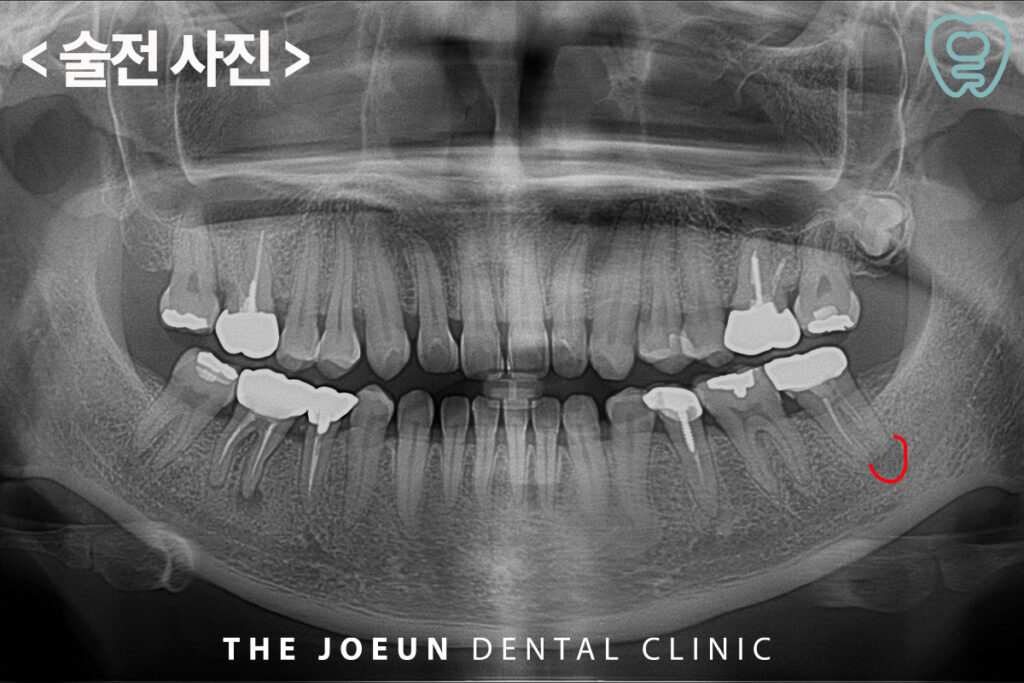

오늘은 신경관과 가까이 있는 치아 뿌리의 염증으로 인해 발치 후 충분한 기간을 기다려준 뒤 임플란트를 식립하신 환자분을 소개해 드리도록 하겠습니다. 환자분께서는 전체적인 검진을 위해 내원하셔서 왼쪽으로 식사를 하실 때 간혹 찝찝한 느낌은 있었지만 큰 불편함은 없으셨다는 말씀을 해주셨는데요.

파노라마를 확인해보니 왼쪽 아래 신경치료 후 크라운이 되어 있는 가장 안쪽 어금니의 뿌리에 커다란 염증이 발견되었습니다. 문제는 뿌리의 염증이 아래쪽의 신경관과 매우 가까워 보였는데요.

신경관과의 정확한 위치 관계 확인을 위해 3D CT를 촬영해 보았으나 신경관과 치아 뿌리의 염증이 매우 가까이 위치하고 있었는데요. 정밀한 검진을 바탕으로 발치를 한 뒤, 충분한 기간을 기다려 주어 임플란트 식립을 진행하기로 계획을 수립하였습니다.